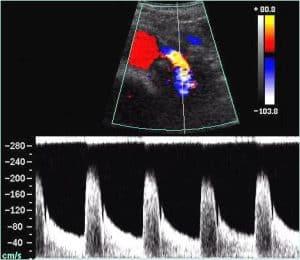

Enhance your understanding of duplex and color Doppler of the kidney, covering renovascular hypertension, renal vein thrombosis, arteriovenous fistulas, and pseudoaneurysms. Learn diagnostic techniques, waveform analysis, and Doppler imaging for precise evaluation of renal conditions and vascular abnormalities.

Discuss arteriovenous fistula including the etiology, symptoms, sonographic findings, and treatment.